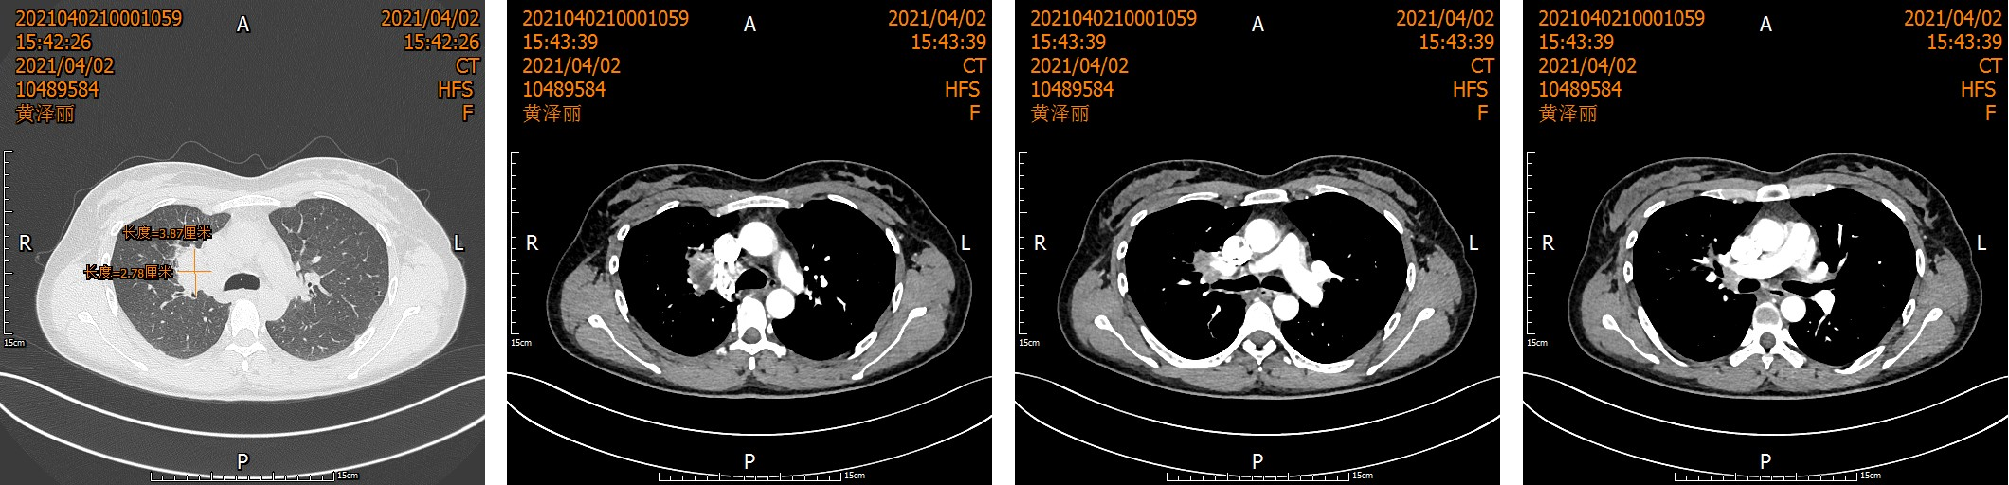

【一拖再拖】女子乳房大面积溃烂流脓,确诊乳腺癌!

任何的肿瘤,都强调早发现、早诊断、早治疗,但临床上还是经常能够见到就诊时就已是晚期的患者。  近日,李女士因发现左侧乳房肿块1年,左侧乳房皮肤溃烂出血3个月到西南医科大学附属中医医院乳腺•甲状腺•血管外科住院治疗。  “我也没有想过会这么...